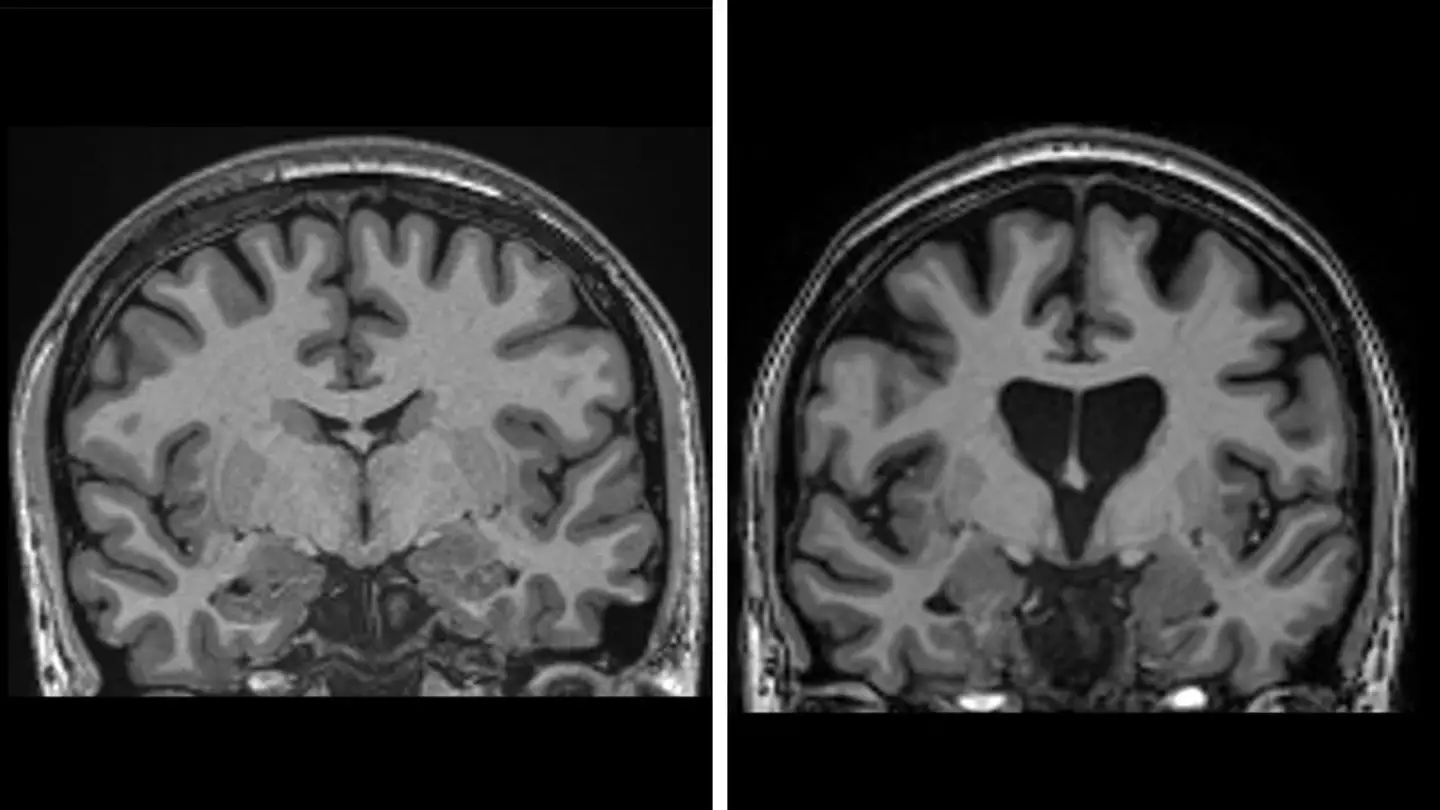

The condition, which affects over 40,000 Americans, according to the Huntington's Disease Society of America, kills brain cells by mutating a protein, known as Huntington's protein, and can be inherited, with a child who has a parent with the gene at a 50/50 chance of having it.

A modified virus is used to introduce new genetic instructions, spreading from brain cell to brain cell and helping them block the protein that causes Huntington’s disease.

The process involved 29 patients, and three years on, data shows fewer brain cells are dying, and disease progression has slowed dramatically.